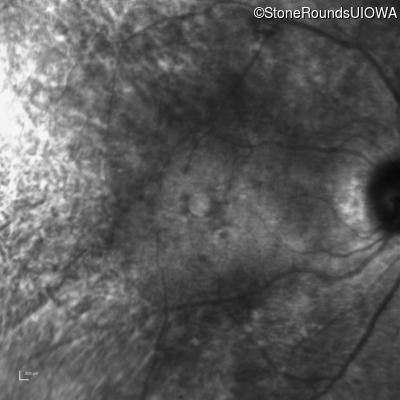

Infrared Fundus Photograph - Right - 20/50 +2

Exemplar